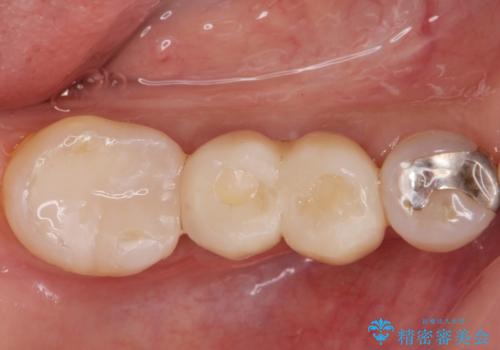

欠損部に1本だけインプラントを埋入しても大きな被せ物になってしまい清掃性が悪くなるので清掃性が良くなるように2本小臼歯用のインプラントを埋入しました。

また1番奥の歯はセラミックインレーで治療を行いました。

無事インプラントが入りました。

インプラント治療をしてもメンテナンスを怠っているとインプラント歯周炎になるリスクがあがるのでメンテナンスをお勧めします。